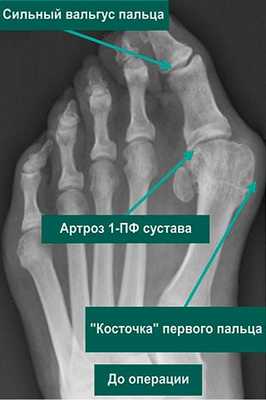

Артроз 1 плюснефалангового сустава — прогрессирующая патология, поражающая хрящевые и костные ткани. Для него характерна тугоподвижность большого пальца и всей стопы, деформация сочленения, боли, усиливающиеся при ходьбе. В отличие от артрозов другой локализации деструктивно-дегенеративные изменения гиалинового хряща часто обнаруживаются у молодых людей. Причинами заболевания становятся гипермобильность суставов, избыточные нагрузки на стопу, в том числе ношение обуви на высоком каблуке.

Для диагностирования артроза используются инструментальные методы, наиболее информативным из которых является рентгенография. Практикуется комплексный подход к терапии патологии: прием НПВП, внутрисуставные инъекции глюкокортикостероидов, иммобилизация большого пальца, проведение физиопроцедур. При неэффективности консервативного лечения пациента готовят к хирургической операции.

Самые сильные боли возникают при артрозе 2 степени. Если на этой стадии патологии обратиться к ортопеду, то от них удастся избавиться с помощью консервативных методов лечения. В дальнейшем выраженность боли снижается из-за полного или частичного сращивания суставной щели. На 4 рентгенологической стадии плюснефалангового артроза сустав становится неподвижным. Врачам остается только диагностировать анкилоз и готовить пациента к хирургической операции.

Диагностика

Опытной диагност заподозрит развитие плюснефалангового артроза при внешнем осмотре стопы. На патологию указывают развивающаяся вальгусная деформация, отечность большого пальца, подгибание стопы при ходьбе. Для подтверждения диагноза проводятся инструментальные исследования. На рентгенологических снимках заметны сформировавшиеся остеофиты, уменьшение размера суставной щели, обызвествленные участки. При необходимости назначается КТ или МРТ. Эти методы наиболее информативны для обнаружения поражений связок, мышц и сухожилий. Проводятся и лабораторные исследования: